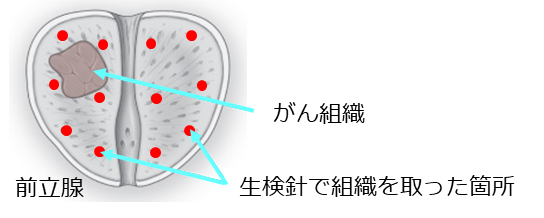

超音波診断機だけでは、大きながんでなければ確認が難しく、多くの場合、前立腺の位置と生検針しか確認することができません。こうしたがんの疑われる部位を正確に事前予測できない中、前立腺全体にまんべんなく複数個所生検針を刺し組織を採取して診断するのが従来型の「系統的生検」です。

従来型の生検では、1度の生検で見つからなかった場合でも、がん組織が無かったのではなく、たまたま針にがん組織が当たらなかったという可能性もありえます。

※生検針が、がん組織に当たらなかった場合のイメージ図:この場合、「がんではない」という診断結果になってしまいます。

本当にがんでなければよいのですが、引き続きPSAが高値で2次検査で再びがんの疑いが出てしまうと、複数回前立腺生検を受けることになり、ようやく前立腺がんが見つかった時には症状が進んでしまっていた、という事態も考えられます。